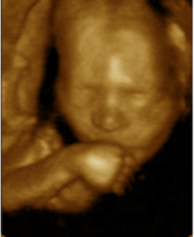

Dos escenas de videos. La de la izq. uno de los gemelos alcanza y "acaricia" la espalda de su hermano. la de la derecha, uno de los gemelos acaricia la cabeza de su hermano.